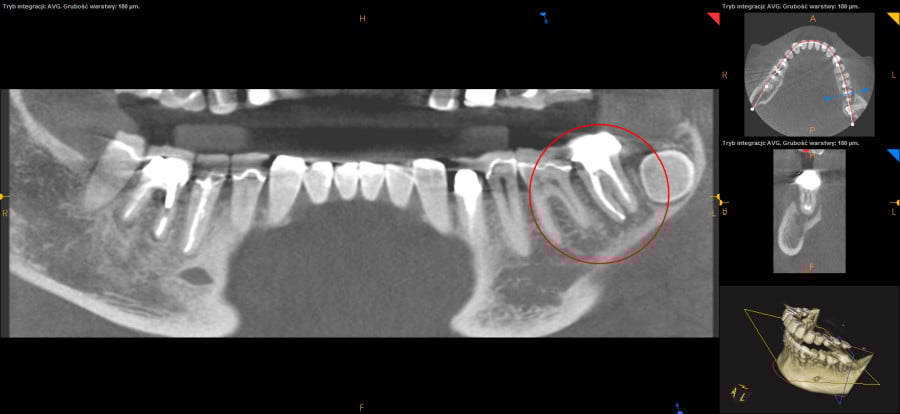

Ten problem najczęściej dotyczy zębów trzonowych żuchwy oraz górnych przedtrzonowców. Może również towarzyszyć wadom zgryzu, w zębach zniszczonych przez erozję, abrazję lub atrycję. Pionowe złamanie korzenia jest trudne do zdiagnozowania. Zdjęcia RTG nie zawsze bowiem ukaże „całą prawdę”. Coraz powszechniej używane obrazowanie CBCT (3D) pomaga w postawieniu diagnozy pionowego złamania zęba lub korzenia.

Do pionowego złamania korzenia zęba może dojść podczas zabiegu leczenia kanałowego poprzez używanie zbyt dużej siły w czasie wypełniania lub oczyszczania kanału. Może być również spowodowane zaklinowaniem się narzędzia w kanale. Pionowe korzenia zęba zawsze prowadzi do usunięcia całego zęba. Dbałość o profilaktykę i terminowe zgłaszania się do gabinetu stomatologicznego z towarzyszącą diagnostyką rentgenowską znaczącą redukuje te ryzyka.